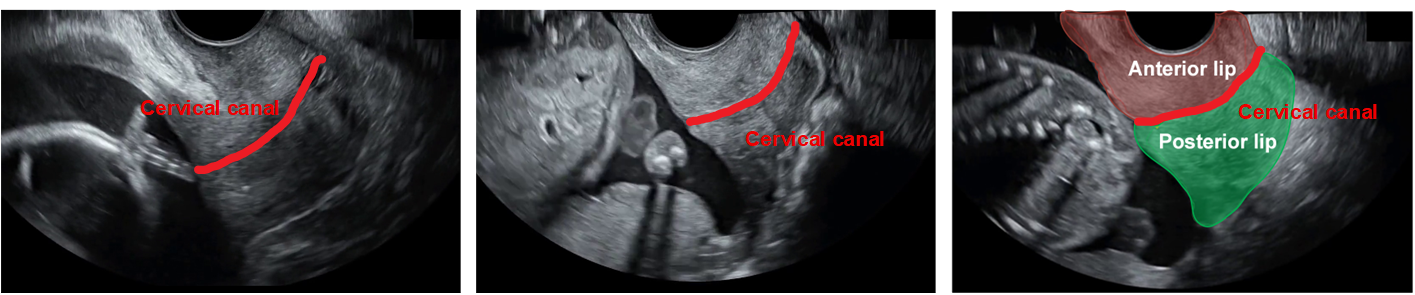

Refer to caption

Figure 1: The anterior and posterior lips are key anatomical structures for identifying the cervix, despite their wide variability in size and shape.